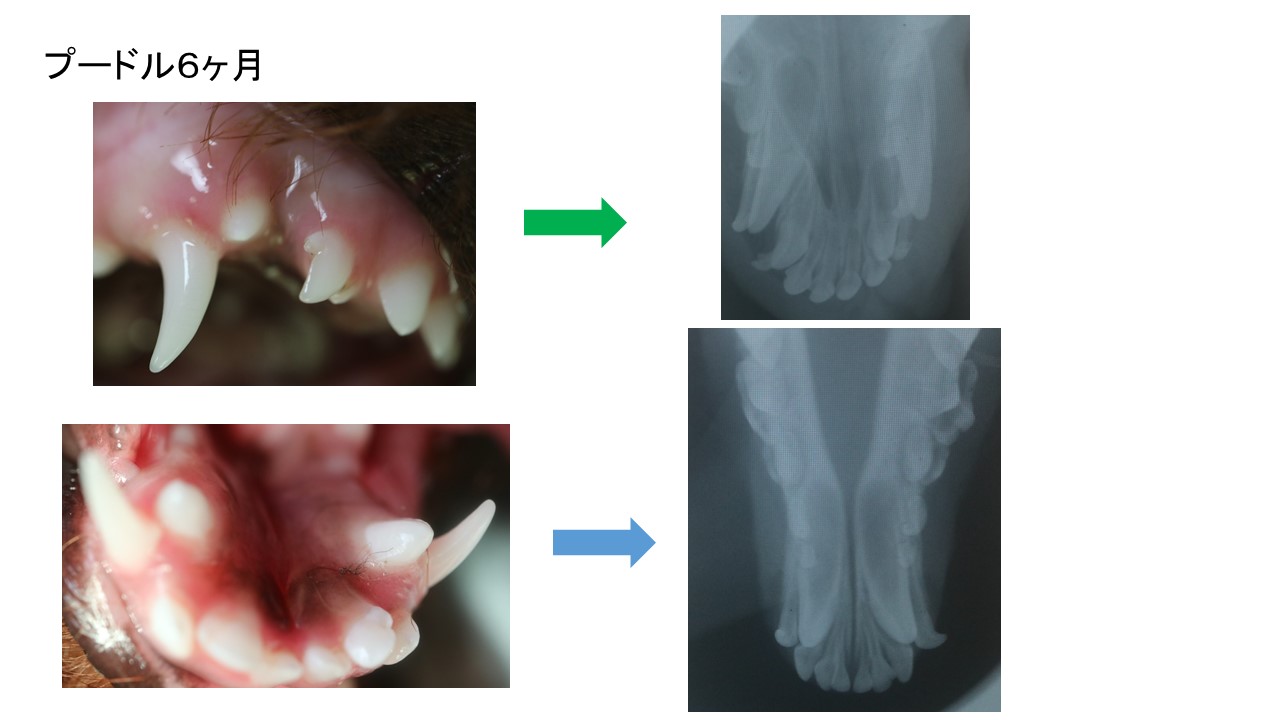

関節炎や血栓の元は歯周病菌からって、

その通り!人と同じか、顎の骨が弱いので

人のそれ以上に感染が酷いのが、犬や猫達(うさぎも🐇)なのです。

歯に歯石が付いてる付いてないの話しでは、

ナイんです。